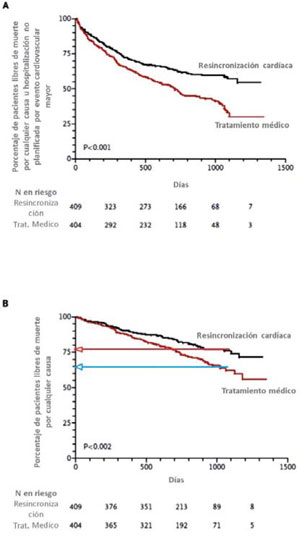

La TRC se aplica clínicamente desde hace más de 20 años. Ha sido demostrada su eficacia en múltiples estudios randomizados y multicéntricos en pacientes con IC CF II-IV, FEVI <35% y BCRI. El primer estudio con estas características fue el MUSTIC23 publicado en 2001. Le siguió el estudio MIRACLE24, con una mayor cantidad de pacientes. En ambos se demostró una mejoría significativa en los síntomas, pero no disminución de la mortalidad total.

El estudio COMPANION14 fue el primero que agregó la terapia de desfibrilación a la TRC, demostrando beneficio en la disminución de la mortalidad con la TRC más el CDI (TRC-D)24. Sin embargo, fue el estudio CARE-HF el que demostró una consistente reducción de la mortalidad de la TRC en ausencia de desfibrilador (TRC-P) (Figura 2)25.

El estudio RAFT26 fue de los pocos que comparó TRC-D con terapia con CDI solo en pacientes con FEVI <30%, CF II-III y duración del QRS >120 ms. Mostró una disminución absoluta de 7% de la mortalidad total u hospitalización por IC con TRC-D.

El estudio MADIT-CRT27 randomizó pacientes con IC CF I-II, FEVI <30% y duración del QRS >130 ms a TRC-D y a desfibrilador solo. Mostró una reducción del punto final combinado de mortalidad y descompensación de IC, sugiriendo que los pacientes en estadios precoces de IC también se benefician de la TRC. Este concepto fue reafirmado en el estudio REVERSE28, que mostró beneficio en los síntomas con la TRC en pacientes con IC CF I-II.

La (Tabla 2) muestra las características de los estudios más importantes, los criterios de inclusión, los puntos finales y sus resultados.